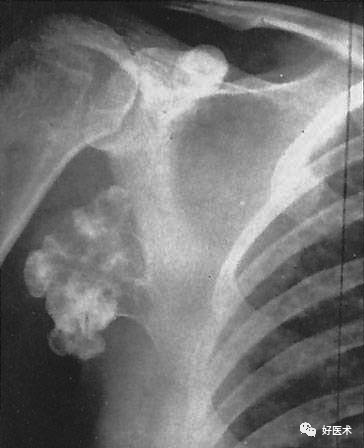

110张经典x线片影像诊断,夜班医生必备纯干货!

佝偻病

佝偻病图片